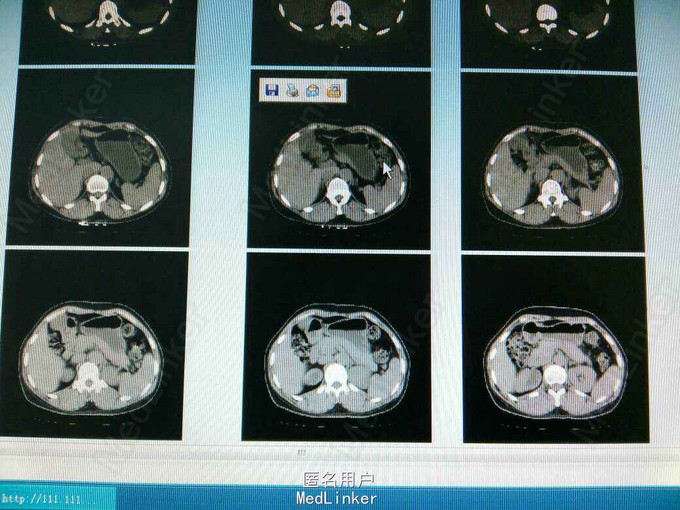

患者,女,51岁,因排尿不适来我院行B超检查发现右侧输尿管口囊肿。

ct提示右侧双肾输尿管畸形,输尿管囊肿。总肾功能正常,尿常规正常,未发现结石等异常,右上位肾脏及输尿管扩张。